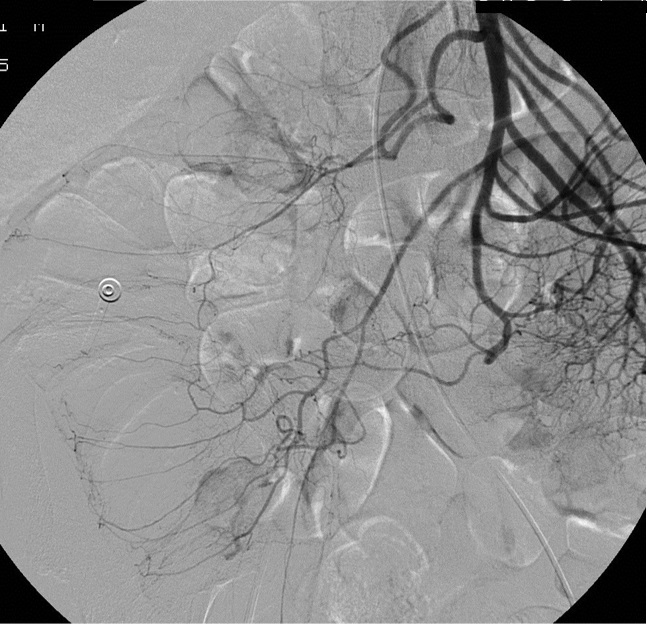

病例二:结肠憩室急性大出血(微导管接近出血)

64岁 男性 无相关病史。因下消化道出血急诊室就诊。考虑到急诊出血情况下效果差,未进行结肠镜检查。CTA 未显示造影剂外溢,但右结肠/回肠大憩室。临床持续出血和生命体征恶化,介入医生会诊决定进行动脉造影。

如果你能用微导管接近出血点,最好的栓塞材料是什么?

• Coils

造影剂外溢